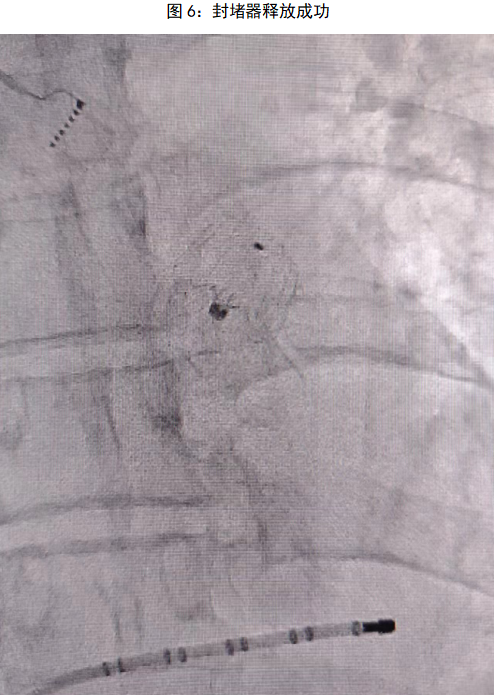

术前对患者进行充分评估,在进行完善的术前检查和全面的术前准备后,手术顺利启动。手术分为两个部分:首先是房颤射频消融,术中使用pentaray导管在Carto3三维系统下,重构建左心房三维解剖图(FAM)同时采集左心房电压基质,在构建右下肺静脉时转为房颤心律,再使用消融导管对左房右肺静脉顶部和侧壁以及左肺静脉嵴部和后壁部位进行逐点消融,左侧和右侧肺静脉均实现单圈隔离,整个射频消融时间控制在90min内。射频消融完成后,朱舜明副主任立即开始左心耳封堵手术。通过在同一个房间隔穿刺位点交换左心耳封堵鞘,造影显示心耳形态呈反鸡翅型,测量左心耳开口为17mm,可用深度为16mm,结合术前三维重建模型及术中心腔内超声(ICE)结果,选择20mmWATCHMAN FLX左心耳封堵器。送入WATCHMAN FLX输送系统,并在ICE及DSA辅助下进行精准定位,ICE多角度查看封堵器位置形态良好,封堵伞展开无漏肩,无残余分流,压缩比16%,牵拉试验稳定,牵拉后无明显位移,符合释放标准PASS原则。随后释放封堵伞,最终成功完美封堵左心耳。